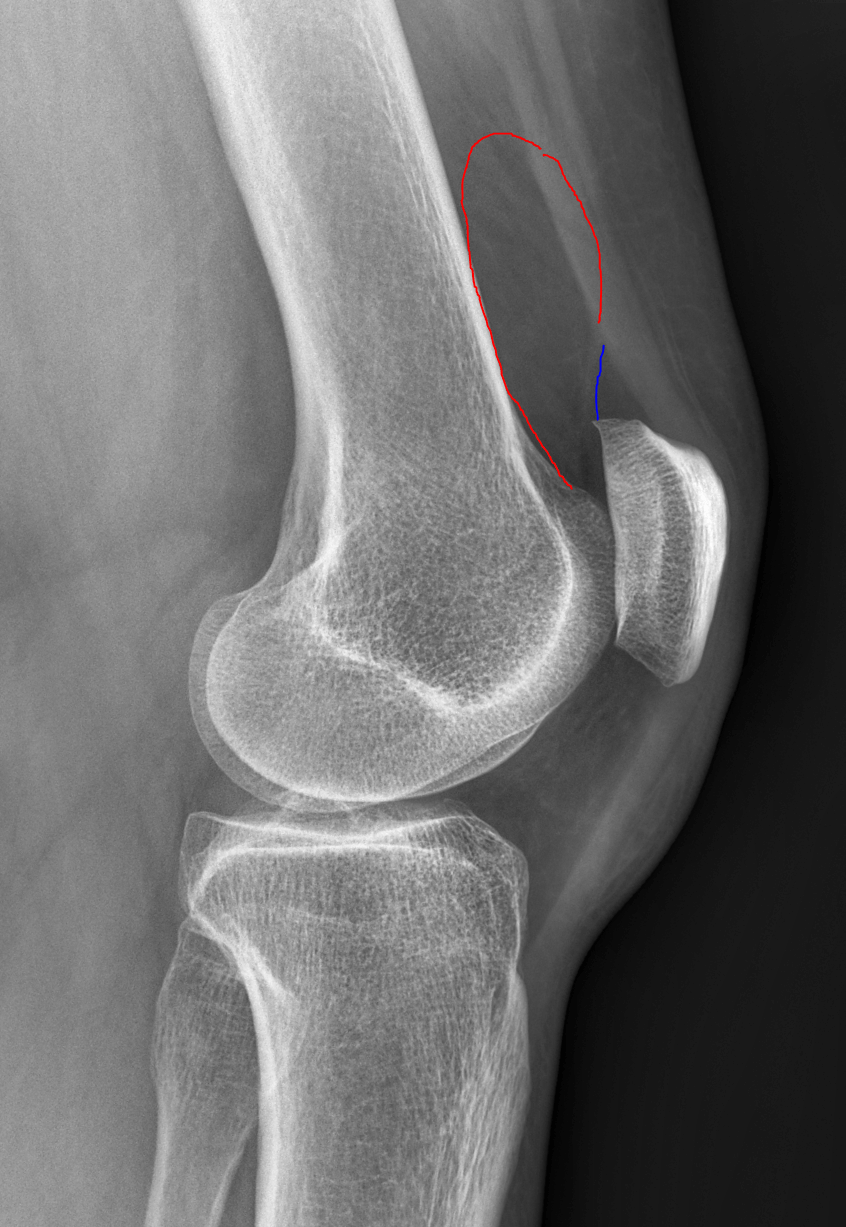

Lateral radiograph of the right knee following the init Openi Large Size Knee Joint Effusion There are certainly other signs of knee joint effusions such as anterior displacement of the patella, but these are only reliably seen on large. Knee effusion, sometimes called water on the knee, occurs when excess fluid accumulates in or around the knee joint. A swollen knee occurs when excess fluid collects in or around your knee joint. Health care providers. Large Size Knee Joint Effusion.

kneejointeffusion Don't the Bubbles Large Size Knee Joint Effusion There are certainly other signs of knee joint effusions such as anterior displacement of the patella, but these are only reliably seen on large. Joint effusion can cause a puffy appearance to your joints along with symptoms like pain and. Common causes include arthritis and injury to knee. Knee effusion, sometimes called water on the knee, occurs when excess fluid. Large Size Knee Joint Effusion.

Knee Joint Effusions Radiology Article Large Size Knee Joint Effusion Health care providers might refer to this condition as an. Joint effusion can cause a puffy appearance to your joints along with symptoms like pain and. A knee effusion refers to an abnormal fluid accumulation within the knee joint. A swollen knee occurs when excess fluid collects in or around your knee joint. The area around your joint may appear. Large Size Knee Joint Effusion.